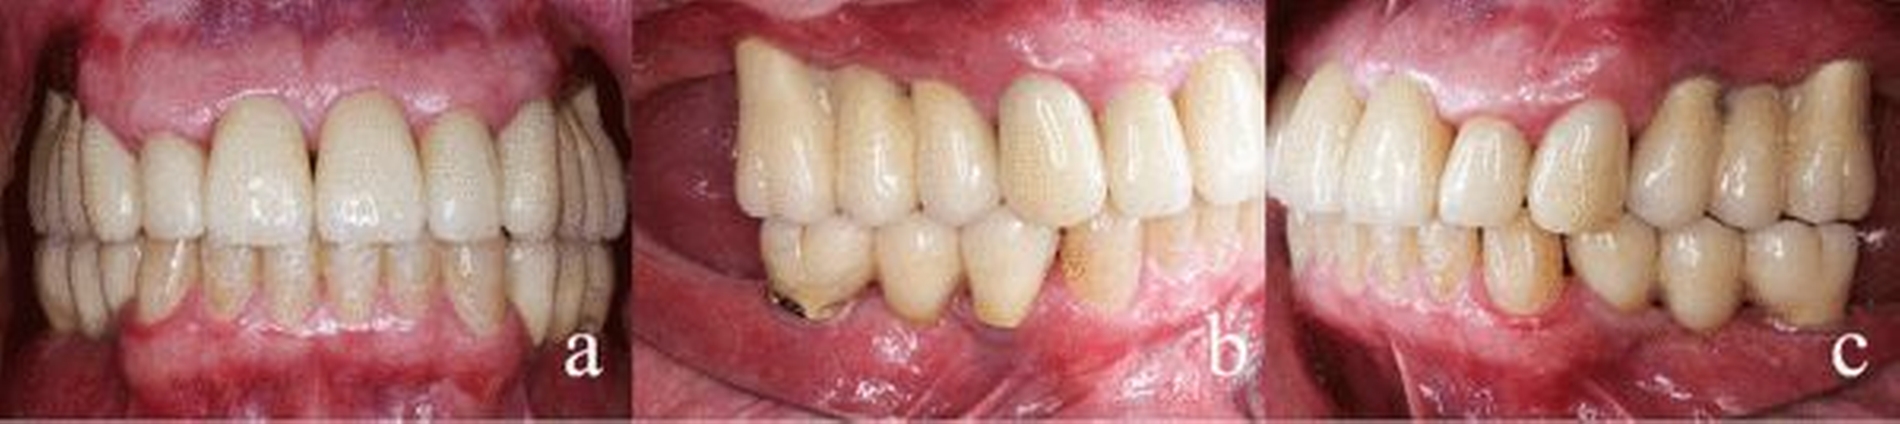

Dem Beginn der zu diesem Zeitpunkt erforderlichen Therapie war eine achtjährige Zahnarztabstinenz und eine damit einhergehende starke Vernachlässigung der Mundhygiene vorausgegangen (Abbildungen 1a-c). Als Grund für die lange Zahnarztabstinenz gab der Patient eine Zahnarztphobie an. Sein äußeres Erscheinungsbild war durchaus gepflegt und stand somit nicht im Einklang mit der oralen Situation. Eine Begründung, warum es zu dem offensichtlich desaströsen Zustand seiner Bezahnung gekommen war, konnte oder wollte der Patient nicht äußern. Die Reaktionen waren auf Nachfrage eher ausweichend und nichtssagend. Der Patient kann als gut situiert bezeichnet werden. Er trat eher introvertiert auf und verbarg seine Zähne beim Reden durch die Lippe.

Der allgemeinzahnmedizinische Befund zeigte ein generalisiert-kariöses Gebiss mit vollständig zerstörten Zähnen im Seitenzahnbereich (Abbildungen 1a-c). Die Zähne 13, 21, 22, 33–43 reagierten beim CO2-Sensibilitätstest positiv. Die restlichen Zähne im Ober- und Unterkiefer zeigten bei Vitalitätsprüfung keine Reaktion. Die Sondierungstiefen lagen im Frontzahngebiet von Ober- und Unterkiefer bei 3–4 mm sowie im Seitenzahnbereich bei größer/gleich 5 mm. Die Ober- und Unterkieferfrontzähne wiesen – im Gegensatz zum Seitenzahnbereich – keine erhöhten Lockerungsgrade auf.

Der Patient stellte sich regelmäßig zu Nachkontrollen vor. Es wurden Termine zur professionellen Zahnreinigung in halbjährlichen Intervallen vereinbart. Zurzeit des hier vorgelegten Berichts lag der Behandlungsabschluss sieben Jahre zurück (Abbildungen 7 und 8a-c).

Besonders der kollegiale Austausch kann in solch einem Fall dazu Beitragen, die von dem behandelnden Zahnarzt ausgehenden vorschnellen Urteile über Persönlichkeit und Verhalten eines Patienten abzuwehren und so eine systematische und strukturierte Therapieentscheidung zu finden. Aufgrund der guten Compliance sowie der deutlichen Verbesserung der Mundhygiene entschieden wir uns für den Zahnerhalt im Frontzahnbereich und eine implantologische Lösung im Seitenzahnbereich. Das zahnärztliche Ziel war, den Patienten nach aufwendiger Rekonstruktion über viele Jahre zu guter Mund-hygiene zu motivieren. Dies konnte durch intensive Aufklärung erreicht werden. Bereits nach den ersten Maßnahmen zeigte sich eine deutliche Besserung der Mundgesundheit. Der Patient begann darauf zu vertrauen, dass eine ihm adäquate Therapie erfolgte. Er entwickelte bald ein gesteigertes Selbstwertgefühl. Schon nach Eingliederung des Provisoriums verbarg er die Zähne nicht mehr hinter den Lippen und gewann sein Lächeln zurück. Seine Gesprächsbereitschaft steigerte sich deutlich. Die Versorgung ist auch nach sieben Jahren stabil (Abbildungen 7, 8a-c). Außer den regelmäßigen professionellen Zahnreinigungen waren keine zahnärztlichen Eingriffe erforderlich. Lediglich ein Chipping der Keramik Regio 46 ist anzumerken. Dies hatte jedoch funktionell und ästhetisch für den Patienten keine Auswirkung.